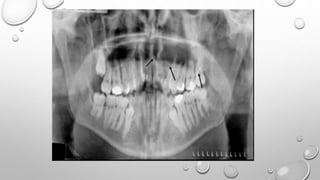

PANORAMICRADIOGRAPHY

• PROVIDES AN EXTENSIVE OVERVIEW OF THE SINUS FLOOR AND ITS

RELATIONSHIP WITH THE

TOOTH ROOTS.